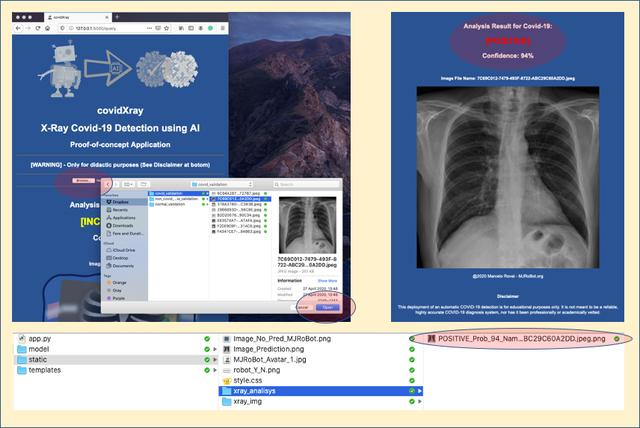

该项目的灵感来源于UFRRJ(里约热内卢联邦大学)开发的X光COVID-19项目。UFRRJ的XRayCovid-19是一个正在开发的项目,在诊断过程中使用人工智能辅助健康系统处理COVID-19。该工具的特点是易用、响应时间快和结果有效性高,我希望将这些特点扩展到本教程第4部分开发的Web应用程序中。下面是诊断结果之一的打印屏幕(使用了Covid-19数据集1图像之一):

乔杜里等人在论文中阐述了该大学开展这项工作的科学依据,论文地址:https://arxiv.org/abs/2003.13145

我们可以选择启动一个Covid的X光图像,它已经在开发过程中用于验证。

步骤顺序如下:

对其中一张有肺炎但没有Covid-19的图片重复测试: